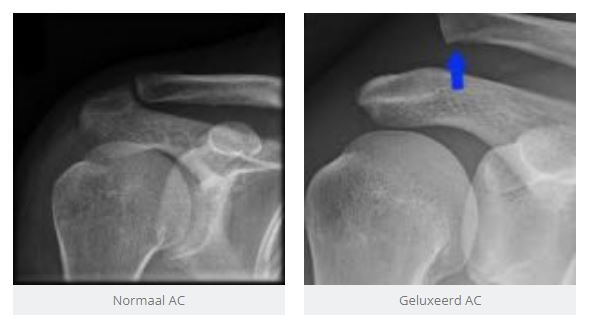

Door een rechtstreekse val op uw schouder zijn de gewrichtsbanden gescheurd die uw sleutelbeen verbindt met het schouderblad. Hierdoor ‘veert’ het sleutelbeen naar omhoog en zien we vaak een trapstand (bajonet stand).

Meestal vragen we een eenvoudige radiografie aan, al dan niet met echo om eventueel geassocieerde peesletsels op te sporen.